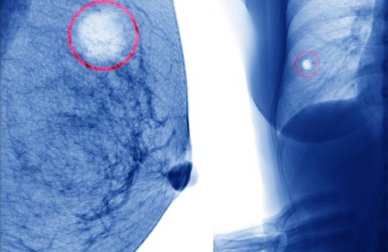

Um cisto mamário é um conjunto líquido no interior da mama.

Ou seja, é como se fosse uma pequena bolsa claramente definida de um tamanho normalmente pequeno, como um grão-de-bico (de proporções menores geralmente), e que contém em seu interior um líquido.

Costuma ocorrer o tipo habitual de cisto, encontrado na maioria dos casos, ainda que também existam cistos que contenham matéria sólida em seu interior.

Existe outro tipo de cistos mamários, os fibroadenomas. Eles não costumam apresentar sintomas e são indolores.

Geralmente, são descobertos quando apalpamos no seio algo duro, móvel e que ao tato parecem ter certa rugosidade, o que ocorre quando são lobulados.

Além disso, deslizam livremente entre os dedos (como um grãozinho que se move) e são igualmente benignos.

Ocorrem devido a uma proliferação excessiva do tecido mamário e, ainda que possam ser confundidos com os cistos que comentamos anteriormente, são diferentes.